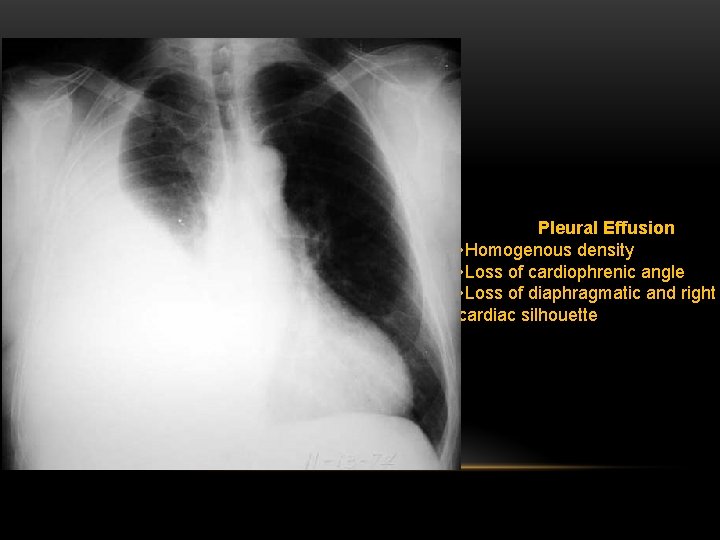

Pleural Effusion Fluid accumulates in the pleural space. Irrespective of the nature of fluid, radiologically they will look similar. Radiological criteria are: Density In dependent portion (Costophrenic angle in PA view). Blunting of costophrenic angle Lack of identifiable diaphragm (silhouette sign principle).

Pleural Effusion • Homogenous density • Loss of cardiophrenic angle • Loss of diaphragmatic and right cardiac silhouette